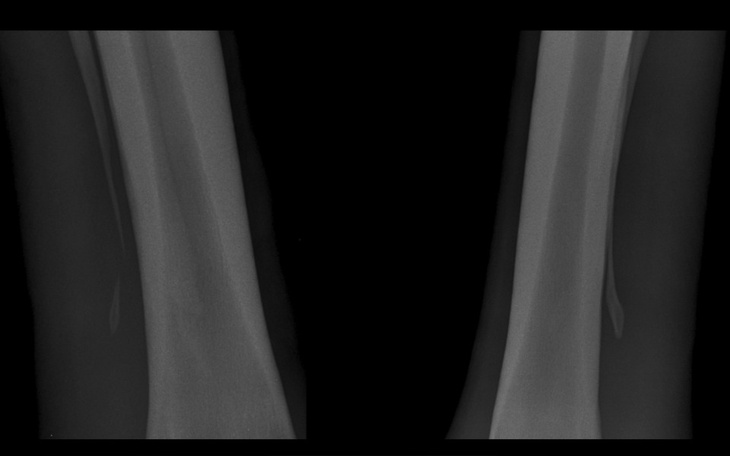

Złamaniu uległ koniec zewnętrznej kości rysikowej (widoczne po lewej stronie powyższego zdjęcia), w drugiej części, jako porównanie widoczny jest rysik wewnętrzny, bez uszkodzeń.

W związku z tym, bardzo proszę o wsparcie w powrocie Zoji do zdrowia - dotychczasowe wydarzenia w moim życiu nie pozwalają mi zaoszczędzić wystarczającej kwoty na jej leczenie - koszt operacji i transportu zdecydowanie przekracza moje możliwości finansowe. Doznany uraz to złamanie dystalnego końca kości rysikowej, przypadkowy uraz padokowy, aktualnie powodujący opuchliznę, ból oraz niechęć do ruchu, wymagający chirurgicznego usunięcia w szpitalu dla koni, odległym o 150km, co dodatkowo generuje koszty transportu konia do kliniki. Będziemy wdzięczne za każdą przeznaczoną na ten cel złotówkę.